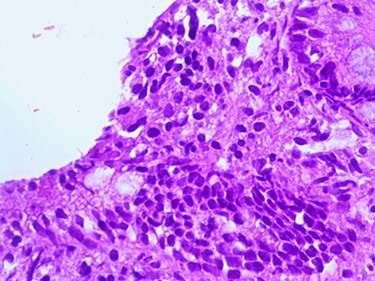

Compatible with Grade B2 on the new grading system for CD classification.

A 3.5-year-old Syrian female was admitted to our hospital with complaints of abdominal pain. She had had several episodes of non-bilious, non-bloody vomiting for 36 hours, and her last normal bowel movement was 2 days prior. Although the patient had a history of sickle cell anemia confirmed by electrophoresis from her first year of life, she had not experienced any sickle cell crises and had not needed blood transfusion or hospitalization. She had no history of diarrhea, either. Family history for celiac disease was positive in a second-degree relative. On admission, her vital signs were normal. Blood analysis indicated low hemoglobin (Hgb) concentration of 9.3 g/dl, but other initial laboratory results were normal. Abdominal examination showed tender distended abdomen. Abdominal ultrasonography suggested the presence of intussuscepted bowel in the right iliac fossa with free fluid between the bowels. Hydrostatic reduction (HR) was not successful, so she underwent surgical reduction. Although no lead points were found, there were multiple enlarged mesenteric lymph nodes and edematous ileocecal junction. On the third postoperation day, the patient again developed similar symptoms, and this time ultrasonography revealed IS in the left side of the abdomen. There was no improvement in symptoms for 24 hours, and ultrasonography revealed the same results after an HR attempt. The patient was operated on a second time, and manual ileoileal IS (Fig. 1) reduction and prophylactic appendectomy were performed. The postoperative course was uneventful, and the patient was discharged 3 days later. Three months later, the patient developed abdominal pain, and the diagnosis of IS was confirmed via ultrasonography. This time, IS reduced over 24 hours of observation. As no lead point was found through the later laparotomy, further investigations were conducted. Upper gastrointestinal endoscopy was performed and showed a mosaic pattern of the duodenum mucosa suggestive of CD. On microscopic evaluation, sections reveal advanced atrophy of duodenal villi with occasional intraepithelial lymphocytes (>30/100 IEL). Crypts show moderate hyperplasia; the lamina propria is infiltrated by diffuse mononuclear inflammatory cell infiltrate. Histopathologically, it is compatible with Grade B2 on the new grading system for CD classification (Figs 2–4). The child was then administered with a gluten-free diet. Eight months later, she visited the hospital as outpatient, and examination revealed she was free of any symptoms.